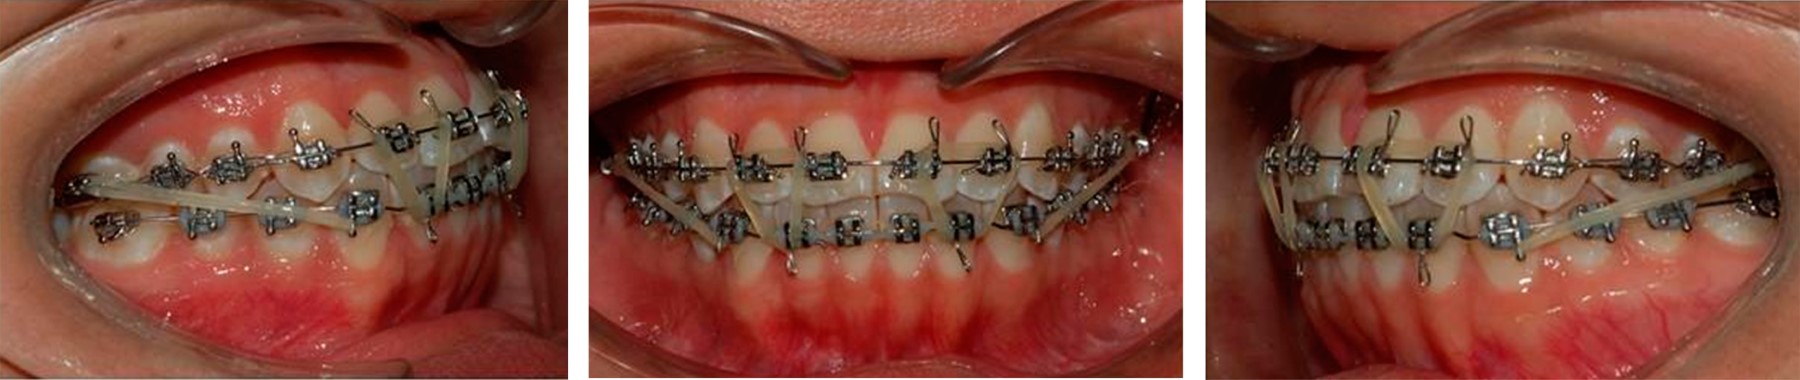

La paciente presentó maloclusión Angle clase I, con mordida cruzada anterior de los incisivos central superior izquierdo y lateral superior izquierdo. Se realizó el diagnóstico con base en las características estéticas, edad y tipo de maloclusión. El tratamiento se efectuó con aparatología fija superior e inferior atendiendo a la perspectiva de Ricketts, con brackets de un slot 0.018"; la alineación y nivelación fue iniciada con arcos de nitinol redondos 0.016". No se ligó del arco el incisivo lateral superior izquierdo porque no había suficiente espacio, por lo que se realizó desgaste interproximal durante la fase de alineación de incisivos para lograr la armonización de la circunferencia del arco y contribuir a una retroinclinación de dientes protrusivos con el fin de alcanzar la normalidad (Figura 4).6

A los siete meses, una vez obtenido el espacio suficiente, se incorporó al arco el incisivo lateral superior izquierdo. A los 10 meses de tratamiento empezó la formación del segmento anterior superior y se completó la aparatología fija en arcada inferior. Se realizó desgaste interproximal para iniciar fase de alineación y nivelación en la arcada inferior. Se decidió colocar recordatorios palatinos en los incisivos superiores con el objetivo de evitar mordida abierta por proyección lingual (Figura 5).

Una vez terminada la alineación y nivelación en ambas arcadas fue necesario tomar una radiografía panorámica y modelos de control para evaluar el paralelismo radicular. Después de recolocar los brackets se reniveló con arcos rectangulares 0.017" × 0.025" de nitinol. Posteriormente, se colocaron arcos de acero inoxidable 0.017" × 0.025" y se terminó asentando la mordida con elásticos clase III de 5/16" con una fuerza de 4.5 oz en conjunto con elásticos triangulares 3/16" 6 oz en los segmentos anteriores (Figura 6).

Figura 4

Figura 5

Figura 6